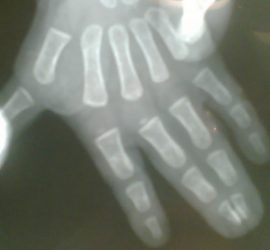

Polidactilias

O que são Polidactilias? Que tipo de polidactilias existem? Polidactilias significam dedos supra-numerários, ou seja número excessivo de dedos. Geralmente, o dedo supranumerário não apresenta desenvolvimento completo. É a segunda deformidade mais frequente asseguir à sindactilia Podemos dividir a deformidade em 3 tipos: Polidactilia radial ou do polegar (existência de […]